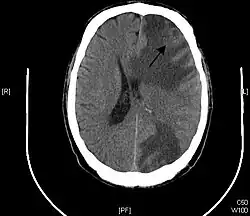

Brain metastasis in the right cerebral hemisphere from lung cancer shown on T1-weighted magnetic resonance imaging with intravenous contrast.